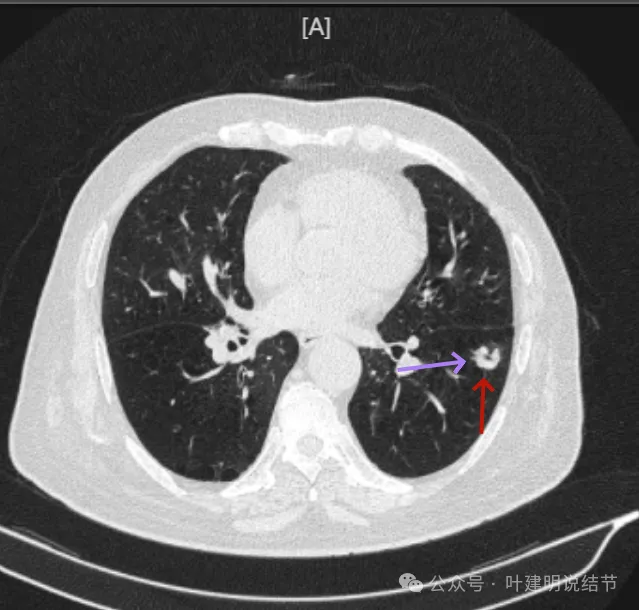

冠状位见病灶基本实性,小血管进入明显,囊壁厚薄不均,囊腔内壁不光滑,表面浅分叶。

矢状位显示较强的收缩力的样子,表面明显棘突的样子,而且囊壁密度杂乱,伴浅分叶征以及胸膜牵拉征。

前后最明显层面对比:

间隔才三个月,明显感觉更不舒服,更像恶性了些。

我的意见:

左肺下叶囊腔型病灶,囊壁厚薄不均,有浅分叶、有血管进入、有棘突征,贴近叶间裂,夜间胸膜有牵拉凹陷,影像表现是非常典型的恶性囊腔型肺癌的表现。而且对比6月份病灶有所进展,建议尽快考虑外科手术切除。肺功能情况如果欠佳,由于位置靠近肺的外周,单孔胸腔镜下局部切除一般是吃得消的,效果肯定好于立体定向放疗或者消融,毕竟病灶是完全能够拿掉的。意见供参考!